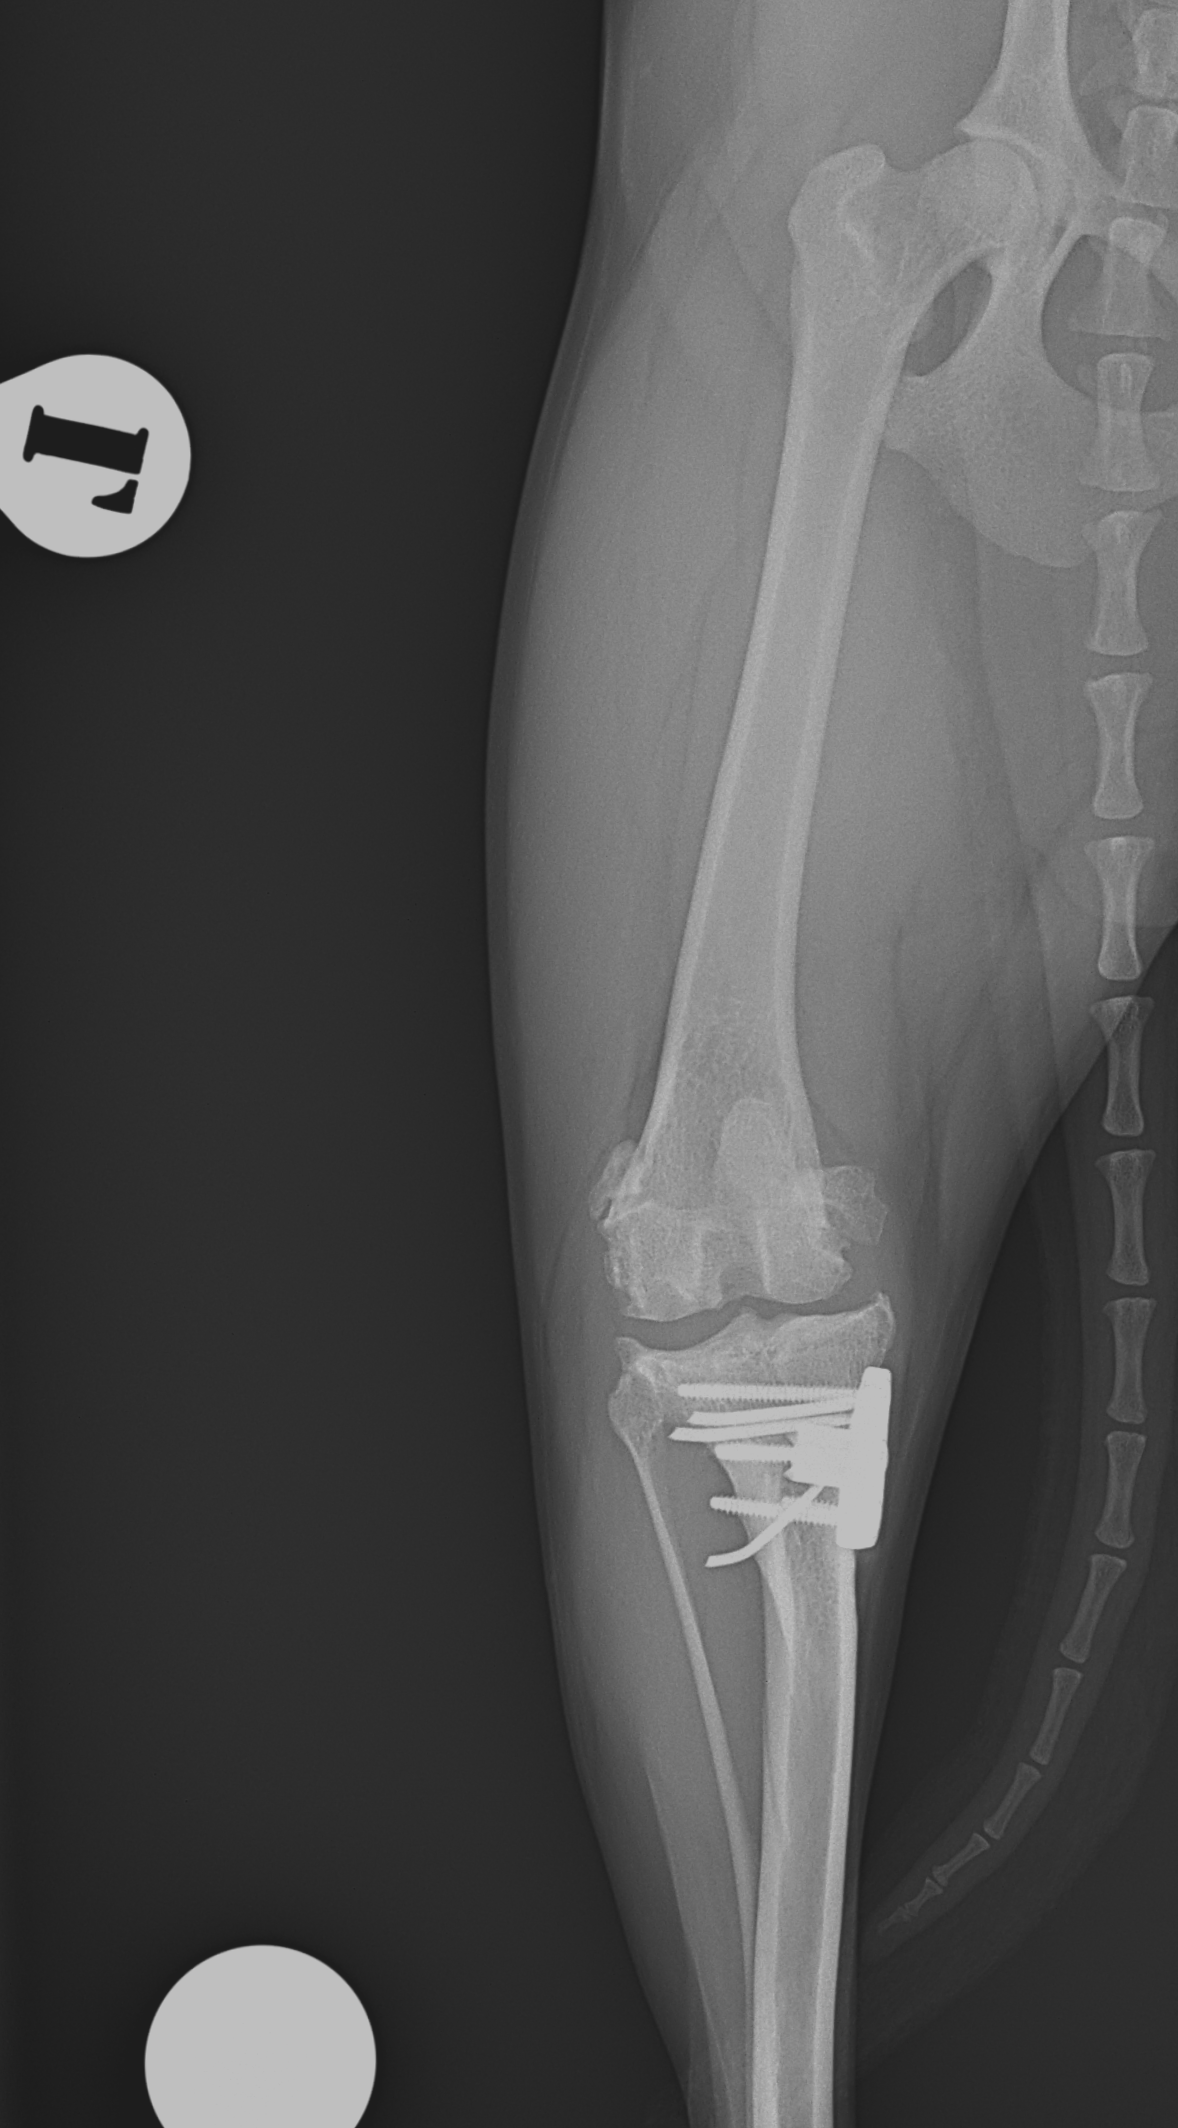

膝蓋骨内方脱臼+前十字靭帯断裂 PGR#21+CBLO #251

過去に膝蓋骨内方脱臼G4で手術を受けている患者さんが、急に跛行を呈するようになったとの事。関節炎が顕著であり、前十字靭帯断裂の併発も疑われます。ファットパッドサイン陽性、脛骨圧迫試験陽性、脛骨ピボット圧迫試験陰性でした。大腿骨滑車のリプレイスメントとCBLOで対応しました。